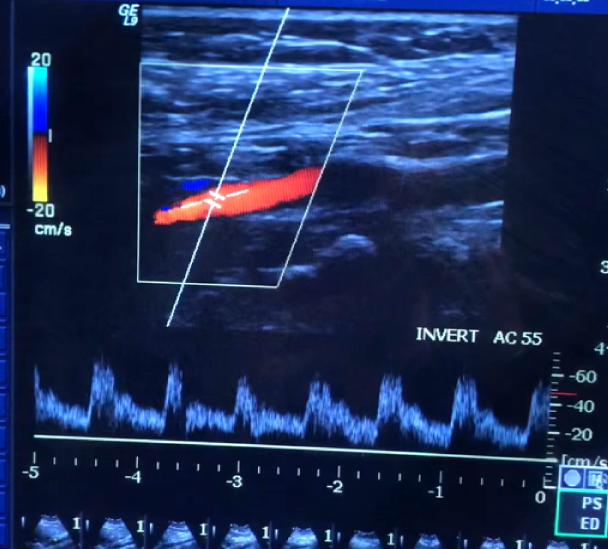

Based on the waveforms, which vessel do they belong to?

CCA

Identify the vessel